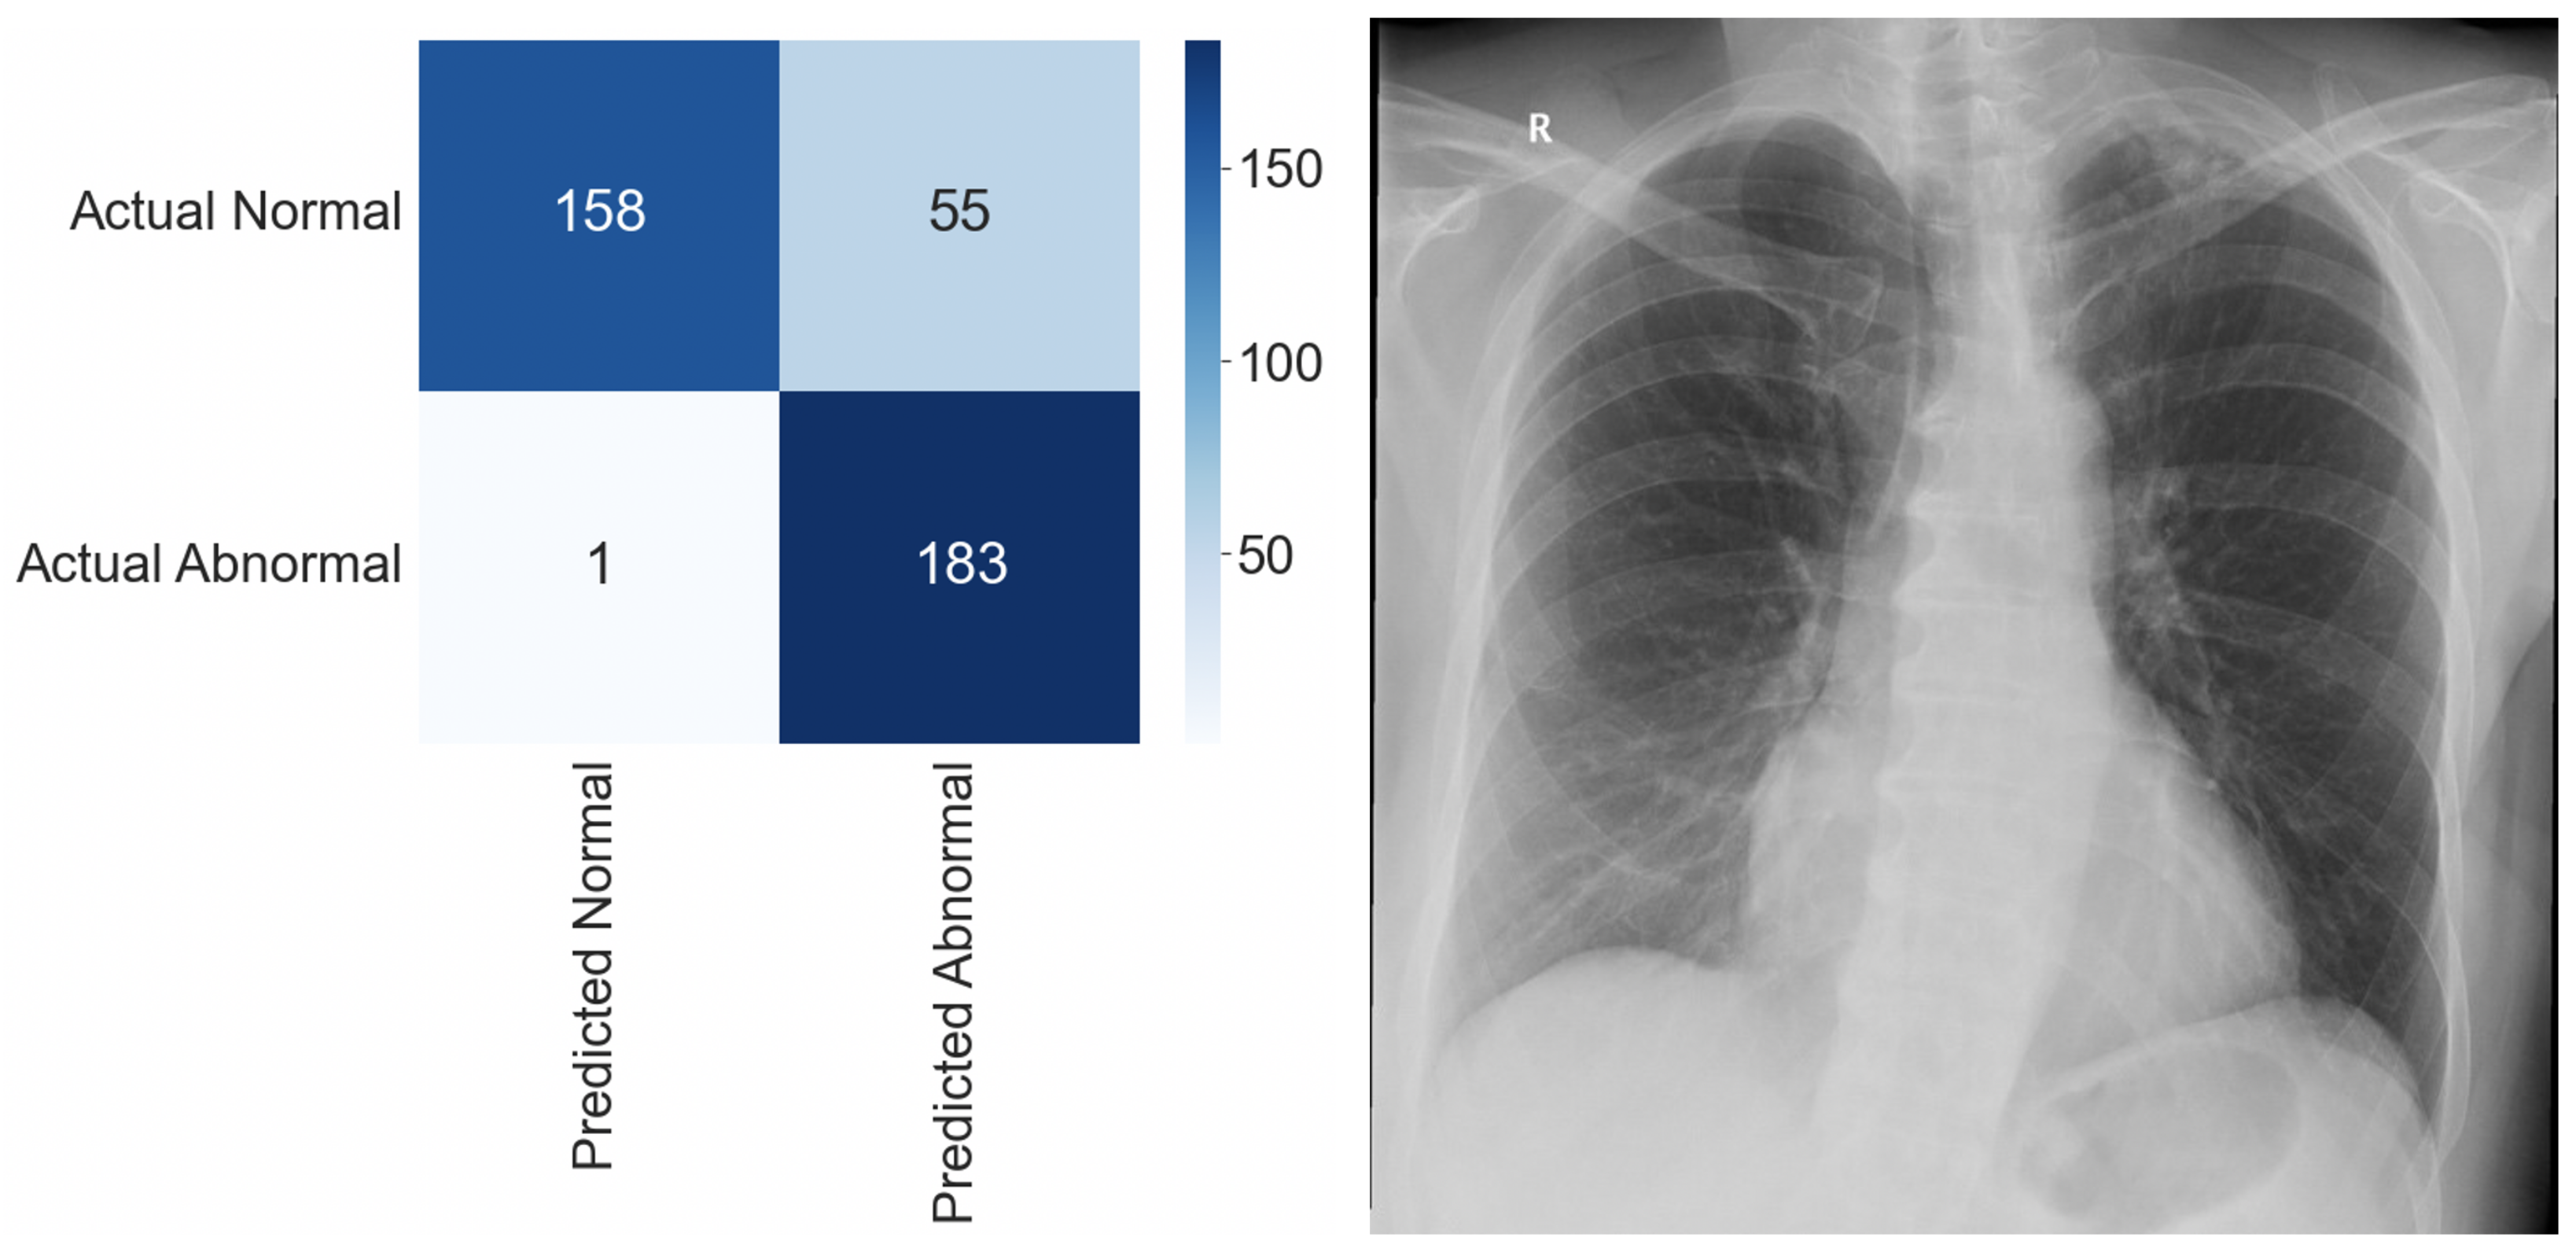

For the initial internal test, we used 397 CXRs that were not observed during the model training. Selected images were retrospectively assessed by three independent radiologists. The ground truth was determined by 100% agreement. The results of the internal test are shown in Table 1. Figure 2 shows an image involving a rib fracture that DLAD incorrectly classified as a scan without any abnormality.

Table 1.

Performance of DLAD during internal test.

Figure 2.

Confusion matrix and a false negative image that DLAD incorrectly classified as a true negative during the internal test. The CXR scan in high quality can be found in the Appendix A (Figure A1).

Of the selected images, 213 (53.65%) were reported as normal and 184 (46.35%) as abnormal. DLAD software correctly interpreted 338 images (85.1%), with only one image resolving in a false negative outcome (FNR = 0.0054). A higher false positive rate (FPR = 0.2582) is an expected occurrence. Considering that DLAD software is intended to serve as a decision support system, this outcome is considered rather desirable.